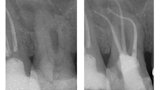

Vyplachování zahnutých kanálků